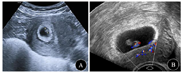

急查妇科彩超示:宫腔内见24 mm×18 mm妊娠囊,见胎芽及心管搏动(图1),右侧输卵管间质部探及17 mm×16 mm妊娠囊回声,内见卵黄囊,腹腔内探及大量游离积液(图2)。

术前超声检查示宫腔内妊娠囊,大小24 mm×18 mm,孕囊内见胎芽及原始心管搏动。右侧输卵管间质部探及17 mm×16 mm妊娠囊回声,囊内见卵黄囊。腹腔内探及大量游离积液。